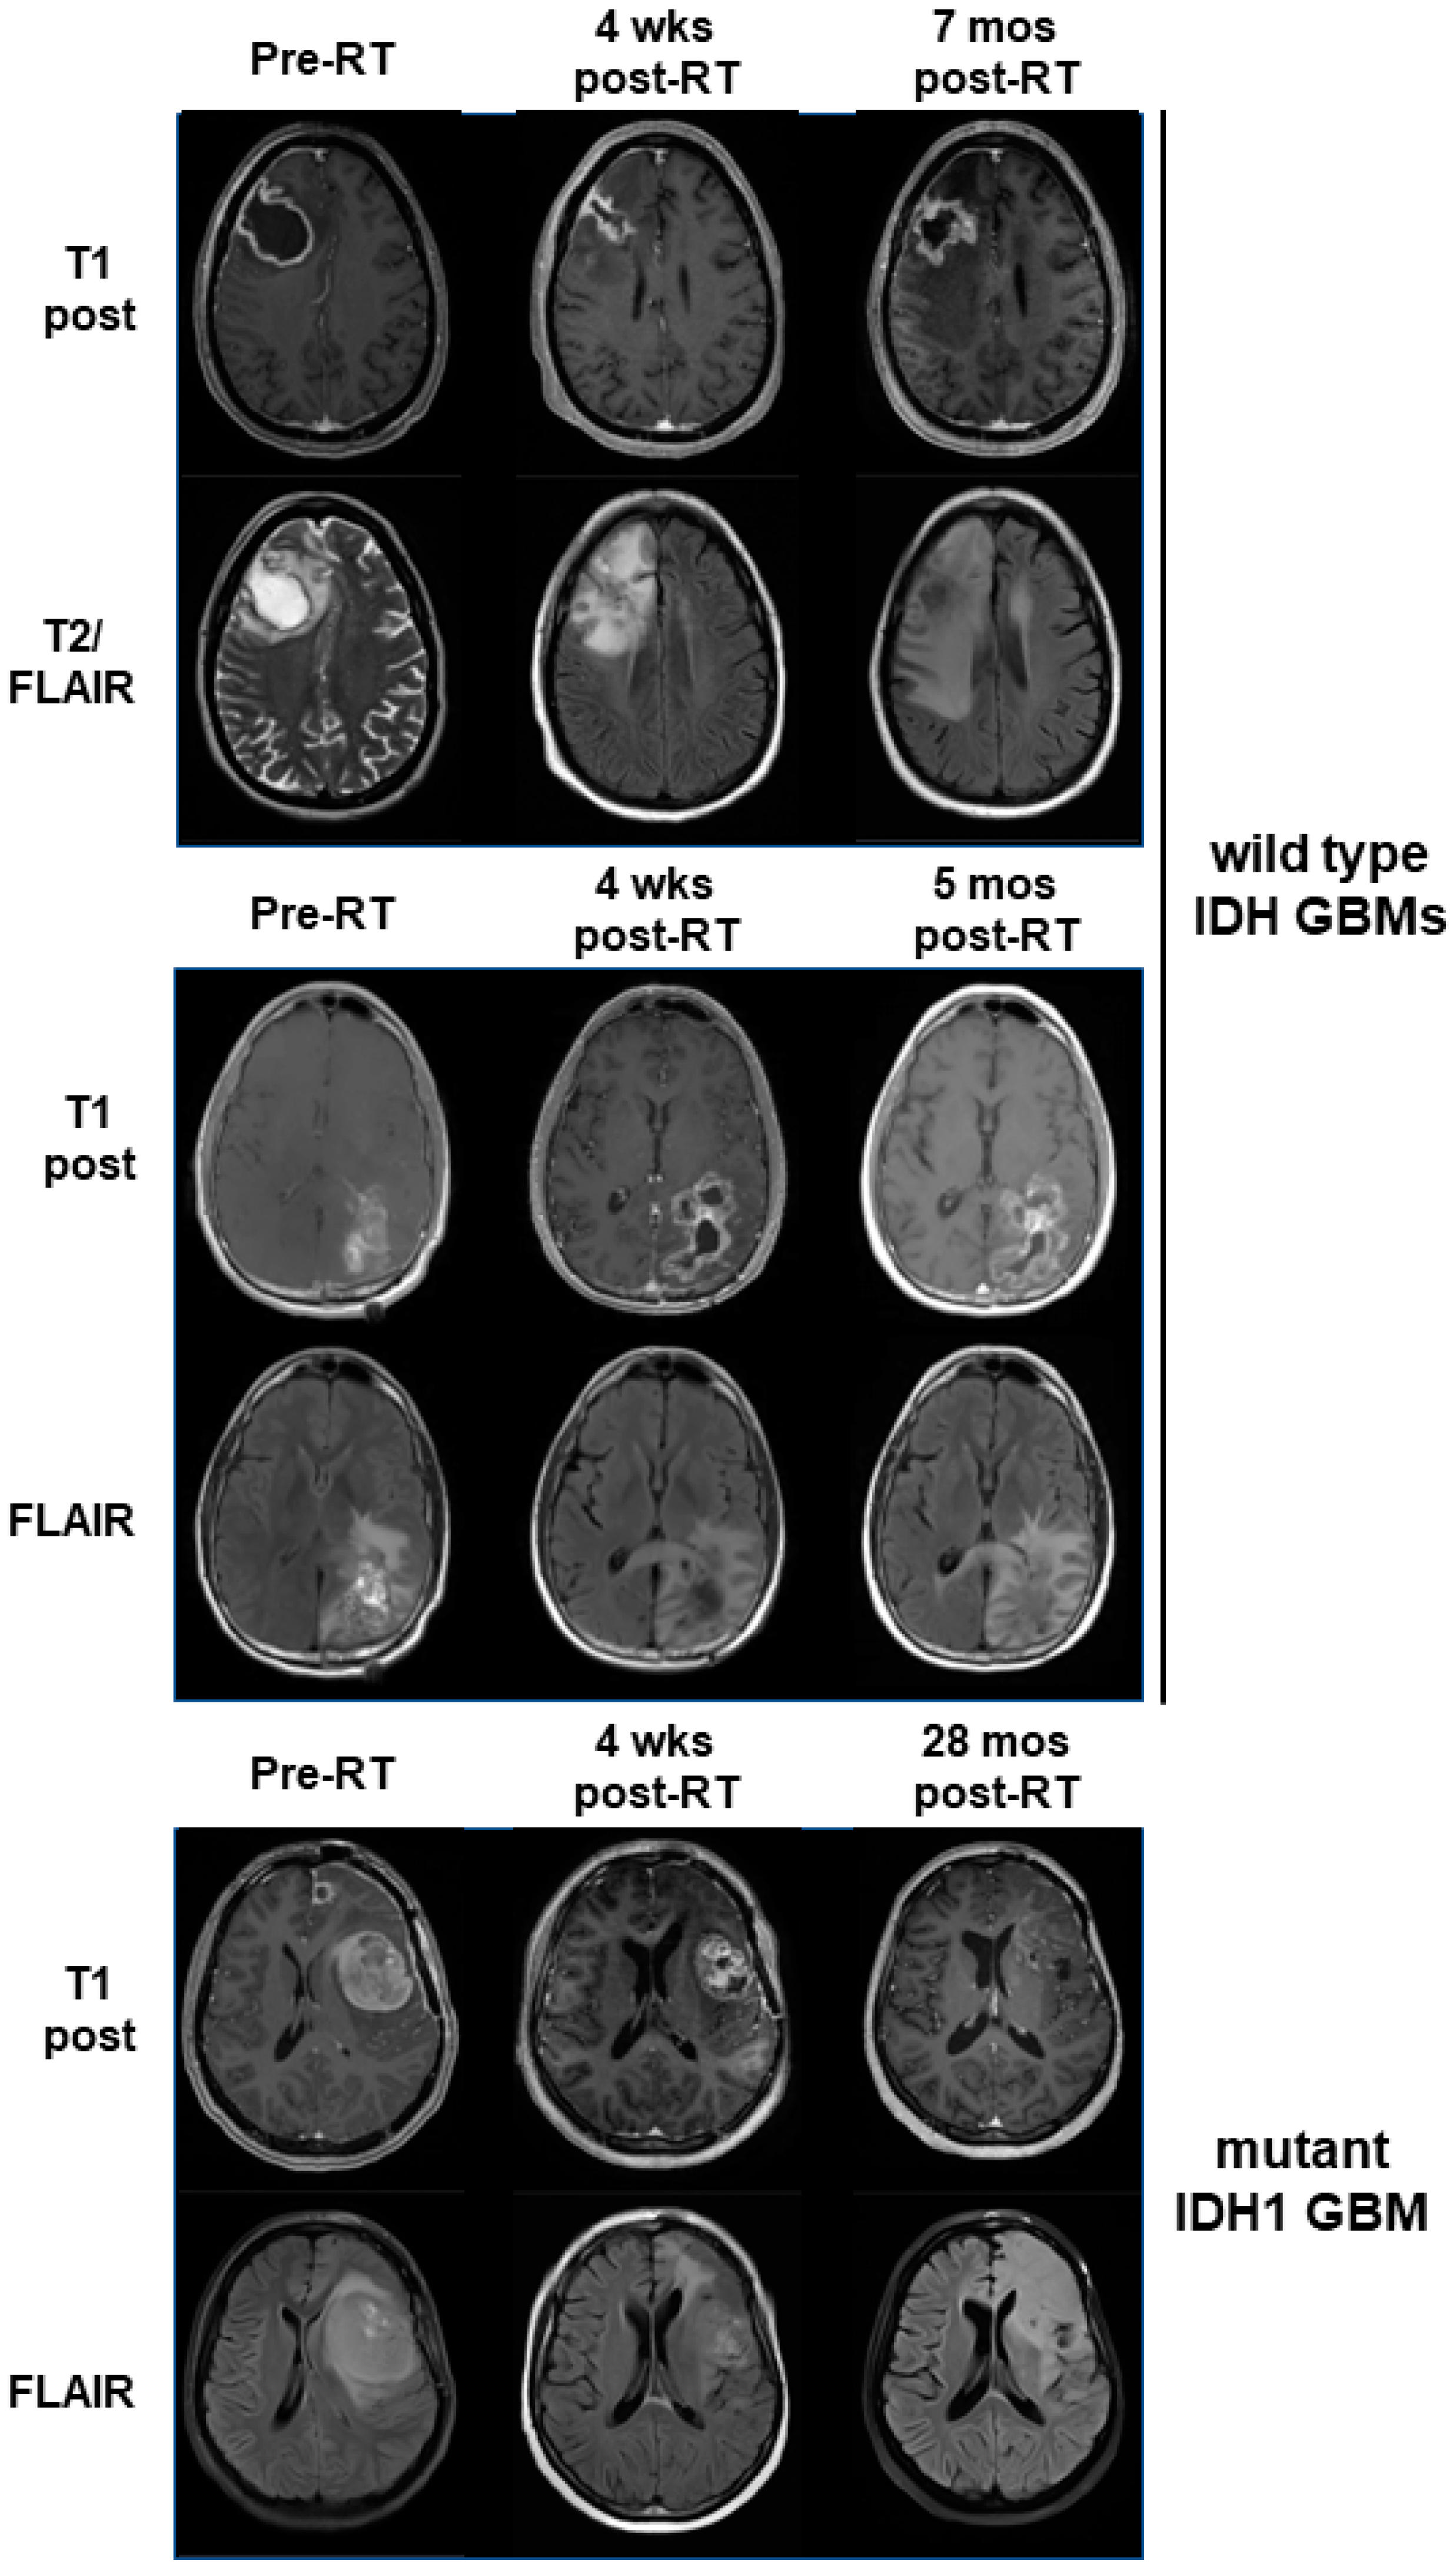

3.4. Mutant IDH1 GBM Shows Greater Response to a Belinostat-Containing Regimen than Corresponding Wild-Type IDH GBMs

- Xu, K.; Ramesh, K.; Huang, V.; Gurbani, S.S.; Cordova, J.S.; Schreibmann, E.; Weinberg, B.D.; Sengupta, S.; Voloschin, A.D.; Holdhoff, M.; et al. Final Report on Clinical Outcomes and Tumor Recurrence Patterns of a Pilot Study Assessing Efficacy of Belinostat (PXD-101) with Chemoradiation for Newly Diagnosed Glioblastoma. Tomography 2022, 8, 688–700. [Google Scholar] [CrossRef]

- Gurbani, S.S.; Weinberg, B.D.; Salgado, E.; Voloschin, A.; Velazquez Vega, J.E.; Olson, J.J.; Shu, H.G.; Shim, H. Remarkable response of a patient with secondary glioblastoma to a histone deacetylase inhibitor. Oxf. Med. Case Rep. 2020, 2020, omaa006. [Google Scholar] [CrossRef]